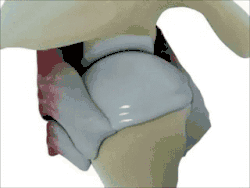

Cross-section of shoulder joint

Structure

The shoulder joint is a ball-and-socket joint between the scapula and the humerus. The socket of the glenoid fossa of the scapula is itself quite shallow, but it is made deeper by the addition of the glenoid labrum. The glenoid labrum is a ring of cartilaginous fibre attached to the circumference of the cavity. This ring is continuous with the tendon of the biceps brachii above.